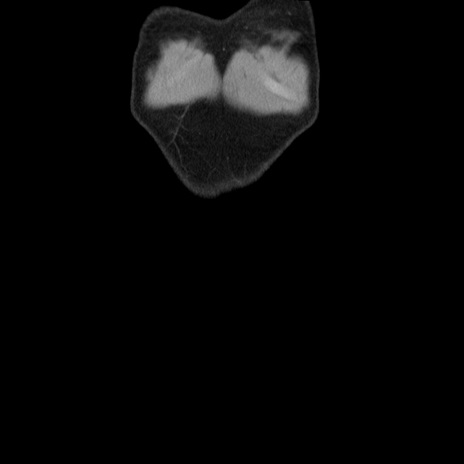

横断像